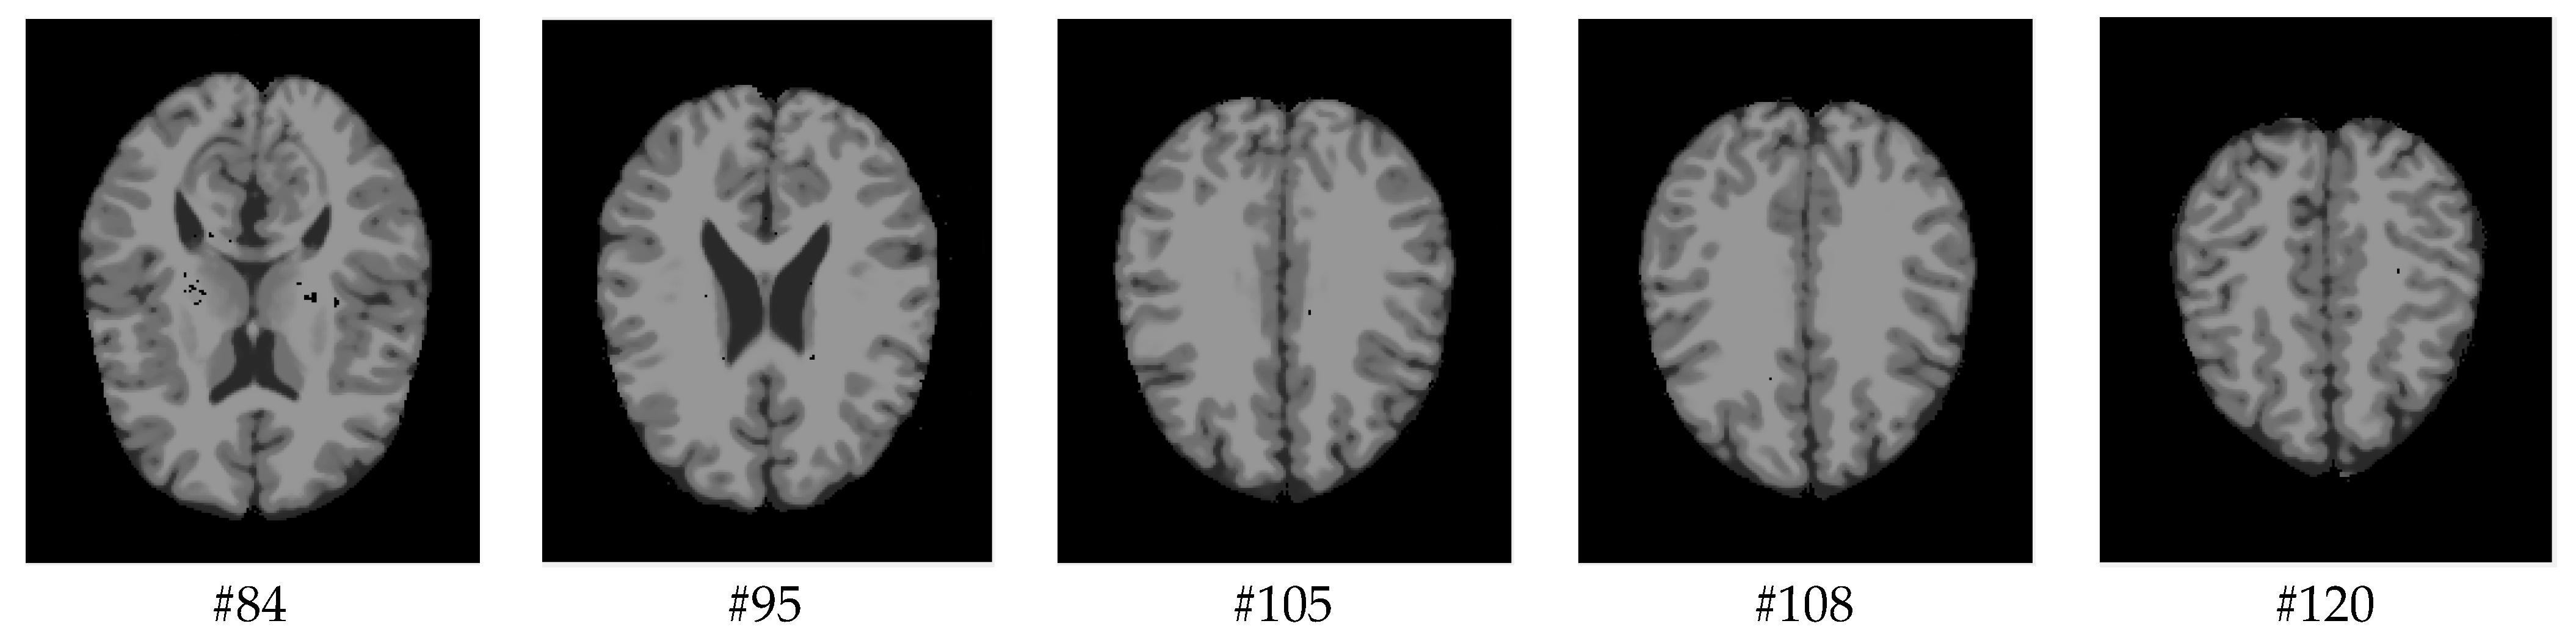

As mentioned before, the images of the first five datasets in Table 3 were used to evaluate the performance of the HMRF-WOA. Figure 1, Figure 2, Figure 3, Figure 4 and Figure 5 show some slices of a T1-weighted image (slices: 84, 95, 105, 108, 120). These brain images correspond to the slices under different types of conditions, such as database type, dimension image, noise level, intensity non-uniformity level, and slice thickness (mm). In Table 1, rows 1 to 5 summarize the parameters of Figure 1, Figure 2, Figure 3, Figure 4 and Figure 5, respectively. Figure 6 represents the ground truth segmentation of slices 84, 95, 105, 108, and 120. In this figure, each column contains the three tissues, GM, WM, and CSF, of each slice. Figure 7, Figure 8, Figure 9, Figure 10 and Figure 11 show the segmentation results, where the four tissues (BG, GM, WM, and CSF) are shown with different colors. The yellow, red, and green colors represent the segmented regions of GM, WM, and CSF, respectively. As we can also see from these figures, the resulting segmented images in Figure 7, Figure 8, Figure 9, Figure 10 and Figure 11 are almost close to the initial images in Figure 1, Figure 2, Figure 3, Figure 4 and Figure 5.

Figure 1. Slices with Noise = 0%, INU = 0% of database 1.